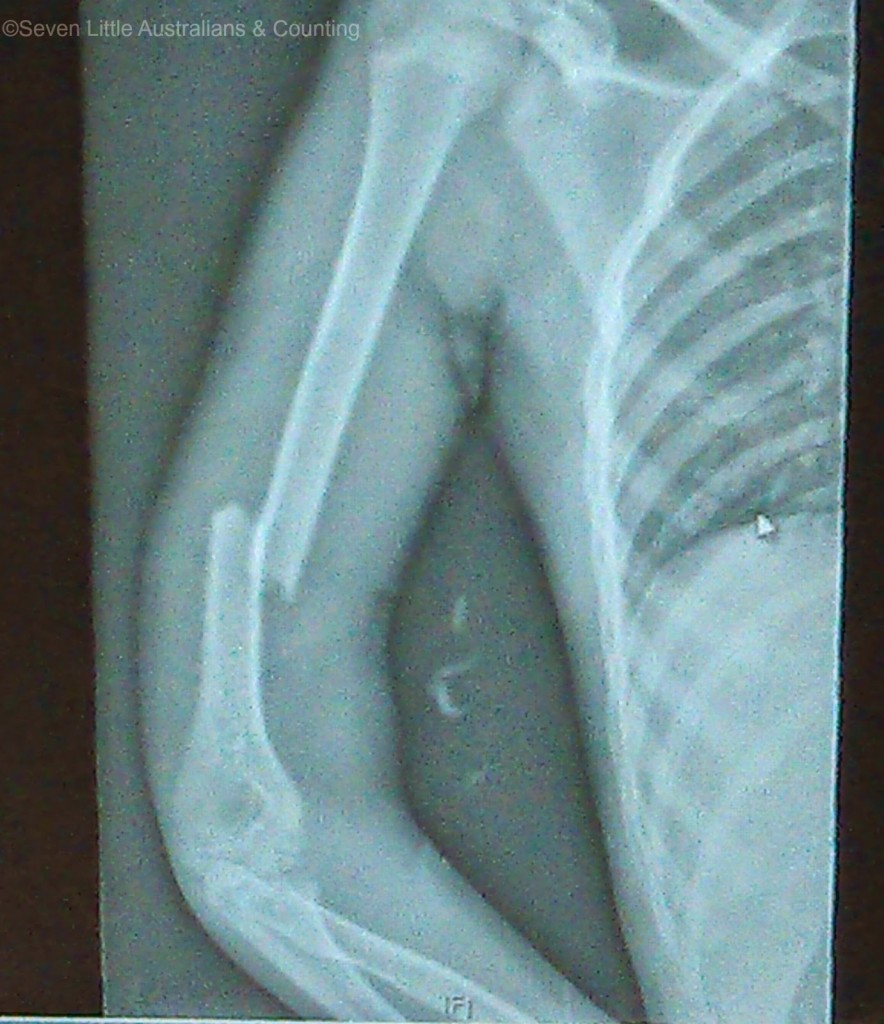

Perhaps it was the sight of us carrying a bleeding ten year old into the hospital, perhaps it was my immediate explanation, “She fell out of a tree from 4 to 5 metres high” but we have never been whisked so fast into Accident and Emergency before. They undertook a complete trauma check on her; spine, neck, chest, pelvis, legs and arm, several times over the next few hours and into the next day. They also constantly monitored her and we were sent for a thorough x-ray. Very, very fortunate the only damage she sustained was to her arm, even my untrained eye immediately knew looking at the x-ray that her arm was broken and I just knew it was going to need surgery.

The surgery was successful and the surgeon was extremely happy with his handiwork, the plate and screws lined the bone up nicely. The surgeon was rather young and when he invited me to look at the x-rays, he rather made me smile, he was quite chuffed with his handiwork, but then he had every right to be proud. Generally surgery to repair a ten year old’s humus bone is not necessary but due to the break in this case it was decided it was, as it transpired, it was the correct decision as when they went in it was discovered that her radial nerve was stretched over the ragged edges of the bones.